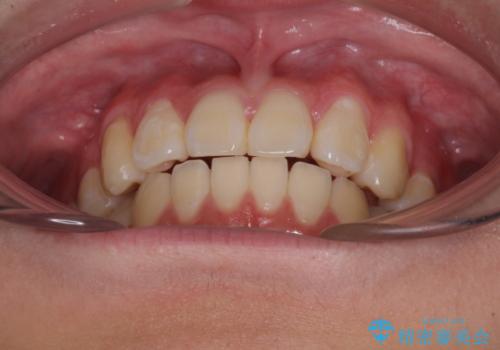

- 八重歯を気にして来院された高校生の患者様です。

ボディーコンタクトの激しい部活動を行っているため、補助装置とインビザラインを用いて、部活動を継続しながら治療を行うこととしました。

八重歯を効率よく改善するため、補助装置を使用して上顎の奥歯を後方に移動させました。

部活動をしながらでしたが、マウスピースをしっかりと装着してくださったので、1年半程度で終了することができました。